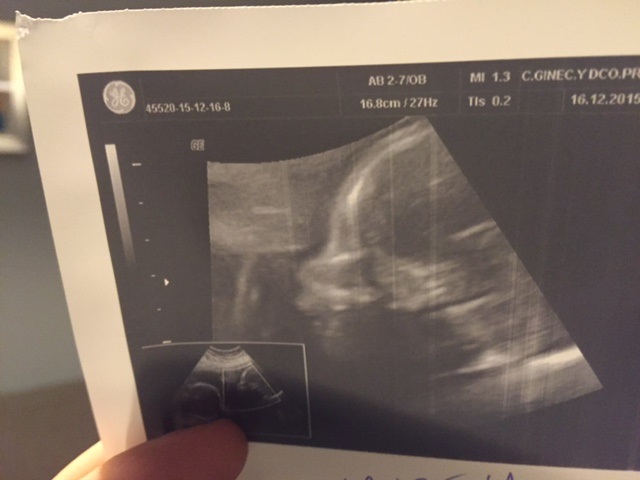

First off, we went back to the doctor this week and everything looks good with the girls. Vera is slightly larger than her sister but we were told that this is normal in fraternal twins since they are in reality not any more alike than any other siblings. Here are their latest ultrasound pictures:

The first picture is of Laura. It's the best we could get and you can see a bit of her face in profile which she didn't want to show. If you look carefully you can see her ear and her eyes but it's difficult. She has her hand in front of her face.

This second picture is of Laura's foot and leg which she had tucked up against her chest. I only hope she is comfortable but I imagine her sister is taking up all the room.

Vera was much easier to see. Here is her little face.

And here she is trying to hide when she got sick of what the ultrasound technician was doing.

| Here is probably the best picture we have gotten of Laura |

| And here is Vera |